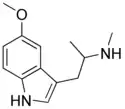

α-Alkyltryptamines are a group of substituted tryptamines which possess an alkyl group, such as a methyl or ethyl group, attached at the alpha carbon, and in most cases no substitution on the amine nitrogen.[17][18][19] α-Alkylation of tryptamine makes it much more metabolically stable and resistant to degradation by monoamine oxidase, resulting in increased potency and greatly lengthened half-life.[19] This is analogous to α-methylation of phenethylamine into amphetamine.[19]

N-Methyl-5-MeO-αMT (α,N,O-TMS/α,N,O-trimethyl-5-HT) | [1-(5-methoxy-1H-indol-3-yl)propan-2-yl](methyl)amine | 4822-13-3 |